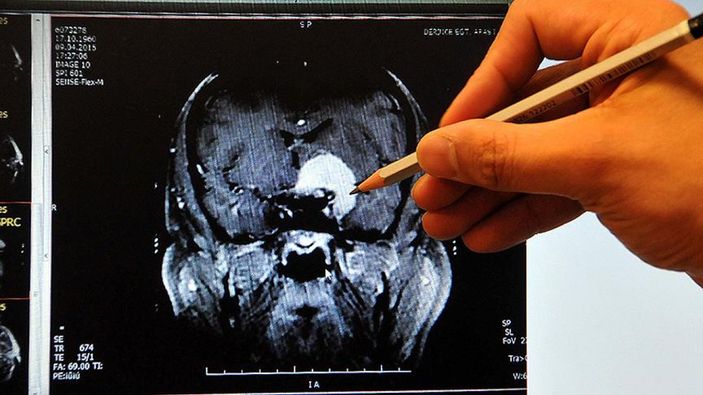

Bunun için önce pıhtı atan hasta kontrol altına alınıyor. Emar ve anjiyolu tomografi uygulamaları ile hasta açısından gelinen süreç netleştiriliyor. Bundan sonra pıhtı atmaması veya atan pıhtının bedendeki tahribatını azaltmak için kan sulandırıcılar kullanılıyor.